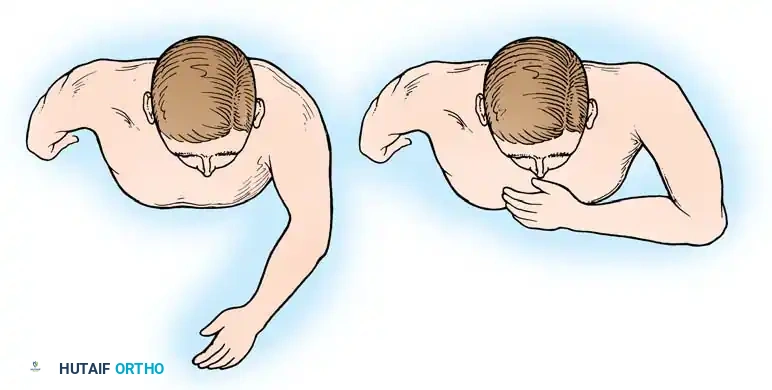

3. Internal Rotation (The Hand-to-Mouth Test): With the shoulder provisionally fixed in the desired abduction and flexion, the elbow is flexed to 90 degrees. The hand should rest comfortably over the ipsilateral chest, midway between the sternum and the axilla. Further flexion of the elbow should allow the tip of the thumb to easily reach the patient's chin and mouth.

The arm is placed into the predetermined optimal position (20-30° abduction, 20-30° flexion, 40° internal rotation). The hand-to-mouth test is performed. Once the position is confirmed, heavy Steinmann pins or K-wires are driven from the lateral humerus, through the humeral head, and into the glenoid vault to provisionally hold the construct.

- Late Rehabilitation: Physical therapy then focuses on maximizing the strength and endurance of the scapulothoracic musculature (trapezius, serratus anterior, levator scapulae), which will now serve as the sole motor unit for the entire upper extremity.